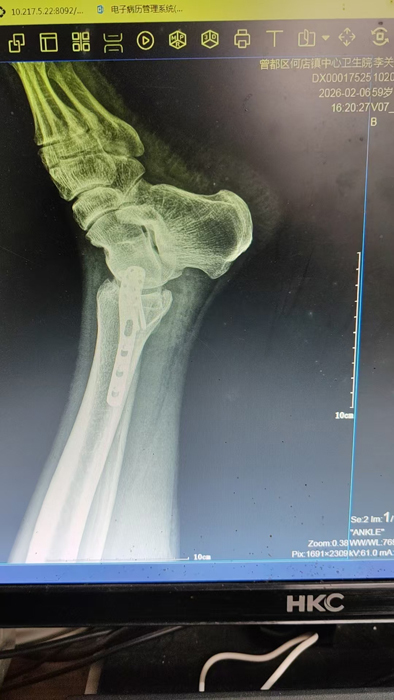

2月4日,何店鎮(zhèn)中心衛(wèi)生院接診一名左踝關(guān)節(jié)外傷患者,經(jīng)影像檢查,確診為左脛、腓骨下段骨折。外科醫(yī)生姜穩(wěn)迅速完成術(shù)前檢查及病情評(píng)估,并與患者及家屬深入溝通治療方案。在患者強(qiáng)烈要求于本院進(jìn)行手術(shù)的情況下,為最大限度保障手術(shù)質(zhì)量與安全,該院特邀請醫(yī)共體牽頭單位——曾都區(qū)人民醫(yī)院脊柱創(chuàng)傷外科專家團(tuán)隊(duì)前來指導(dǎo)。

本次幫扶由曾都區(qū)人民醫(yī)院脊柱創(chuàng)傷神經(jīng)外科主任徐三軍帶隊(duì),專家團(tuán)隊(duì)抵達(dá)后立即完成手術(shù)風(fēng)險(xiǎn)評(píng)估及術(shù)前準(zhǔn)備。手術(shù)過程中,徐三軍主任嚴(yán)格規(guī)范完成各項(xiàng)手術(shù)操作,并同步結(jié)合手術(shù)步驟,為該院外科醫(yī)師詳細(xì)講解骨折手術(shù)的關(guān)鍵要點(diǎn)、操作技巧、術(shù)中注意事項(xiàng)及術(shù)后康復(fù)要領(lǐng)。通過“手把手”的實(shí)戰(zhàn)帶教,專家將豐富的手術(shù)經(jīng)驗(yàn)與規(guī)范的診療思路傾囊相授,讓該院醫(yī)護(hù)人員在實(shí)操中學(xué)習(xí),在過程中成長。